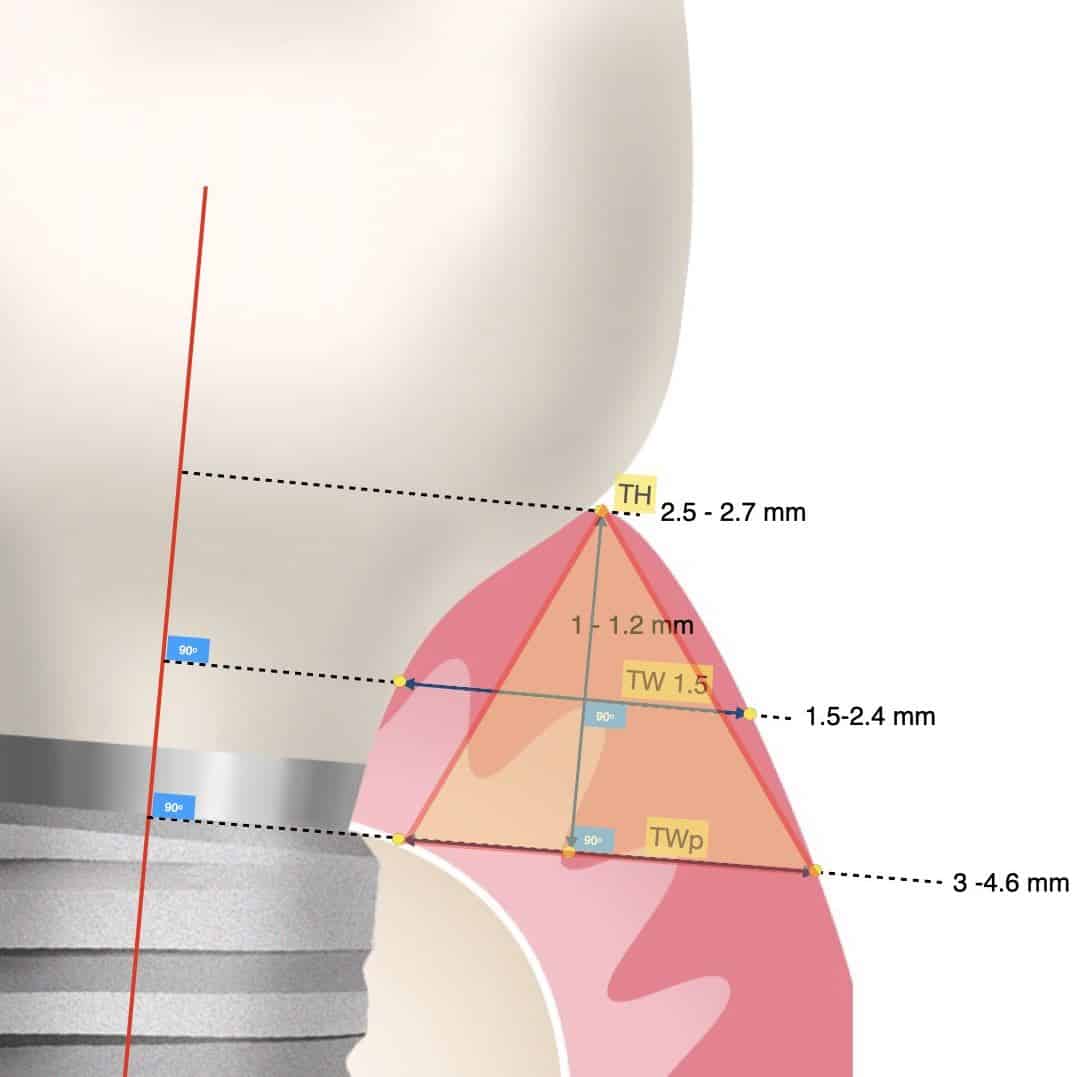

Through measurements of peri-implant mucosa, a consistent finding was always the mucosa being wider at its base than its height, resembling a pyramid.

A consistent finding in peri-implant mucosa dimensions was that the mucosal width at the implant platform was always more than the corresponding mucosa height. So in simple terms, if you draw a line at the level of osseointegration from the implant shoulder to the outside margin of the mucosa, this will always be more than the corresponding height of the soft tissue. In posterior sites the width will exceed the height by a factor of 1.5 to 2. Interestingly, this is the opposite in physiological periodontium, where the periodontal tissue around natural teeth are typically more high than wide. Now in the case of tissue level implants, the corresponding width is to be counted at the interface of the rough surface. Whether tissue or bone level implants, the vertical soft tissue architecture is being established on top of the marginal bone.

Observe the dimensions of the buccal peri-implant mucosa 18 months after implant placement with Guided Bone Regeneration of a self contained buccal bone defect. The overall mucosa before surgery was actually only 1.3 mm thick, but thanks to the augmentation of the bone, there is sufficient "flat land" to establish a wide base of the pyramid (5.1 mm) and the essential soft tissue height (3.5 mm).It's not a townhouse, it's a pyramid, but will do the job!